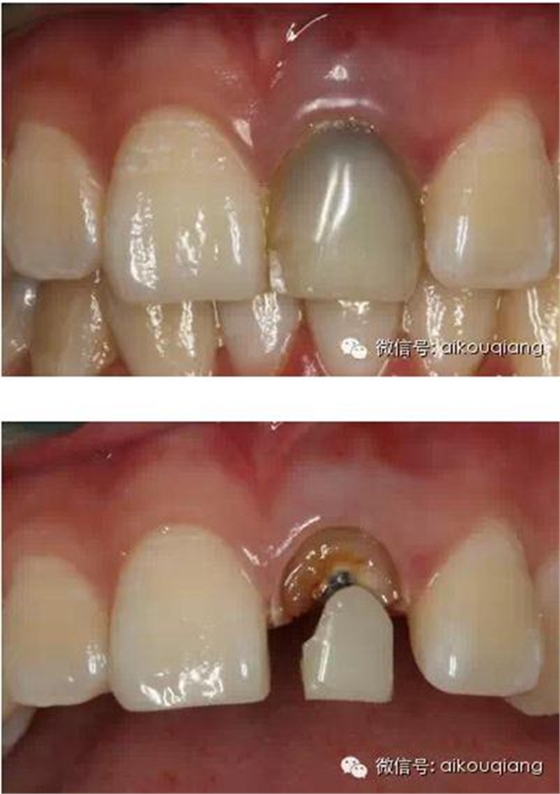

瘺管位置

用MTA修補術后觀